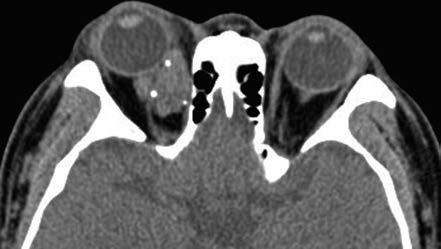

Figure 2 CT imaging of a right orbital venous malformation

Scattered venous stones visible within the lesion.